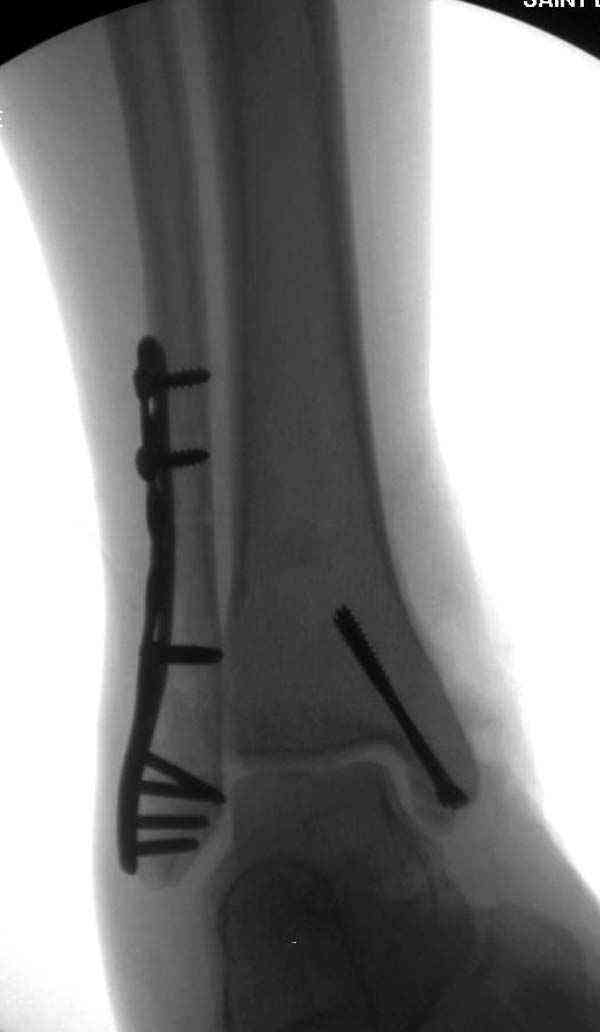

Описанная вами техника "Внутренняя лодыжка фиксирована по Веберу, наружная реконструктивной пластиной с наложением болта-стяжки" существует, но этот подход морально устарел, и применяется очень редко, только при отсутствии имплантов.

Реконструкционные пластины на лодыжке очень грубые, и из-за тонкого слоя кожи над дистальным концом малоберцовой могут осложниться пролежнями кожи изнутри.

Нет первичных снимков, перелом очень низкий и под большим сомнением диагноз разрыва синдесмоза. Медиальная сторона отрепонирована на "хорошо" и, по-видимому, прорезание проволоки произошло во время операции. Без снимков трудно судить о высоте малоберцовой, а лодыжка находится в варусе. Лагирование получилось, но возле тонких шурупов передне-задний шуруп выглядит немного тяжеловато.

Во всех руководствах АО имеется описание техники применения низкопрофильных пластин 1/3 трубки, которые могут быть применены для фиксации наружной лодыжки. Фиксацию проводят кортикальными 3.5 мм шурупами, и если дистальная фиксация недостаточная, тогда усиливают конструкцию созданием hook plate. Сгибая конец пластины на последнем отверстии, внедряют его в дистальный отдел, и тем самым создается дополнительная фиксация.

Здесь несколько частных случаев: перелом голеностопа со сравнительными снимками и разрыв синдесмоза, а также медиальная Hook пластина.